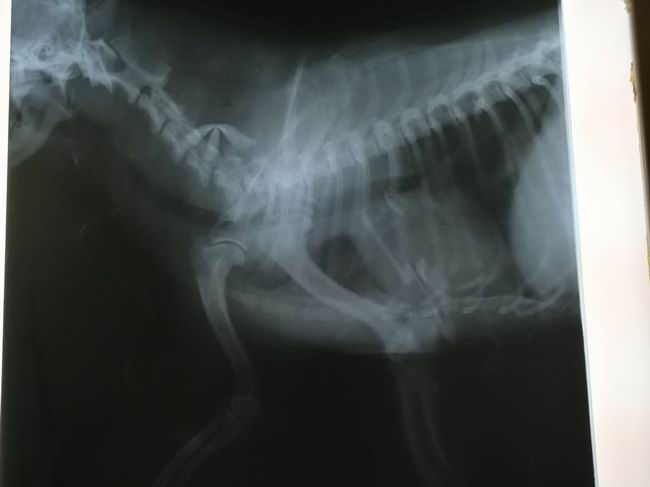

仔仔,9歲,京巴串串,平時腰椎頸椎有問題主人沒有在意,因為一次從床上跳下滑了一腳,后倒地不起四肢僵硬麻痹癱瘓,主人心急如火跑了多處動物醫(yī)院,未見起色,后來到我院經(jīng)趙院長治療,每天都有很大的變化,經(jīng)治療一星期都能站起來跑動。